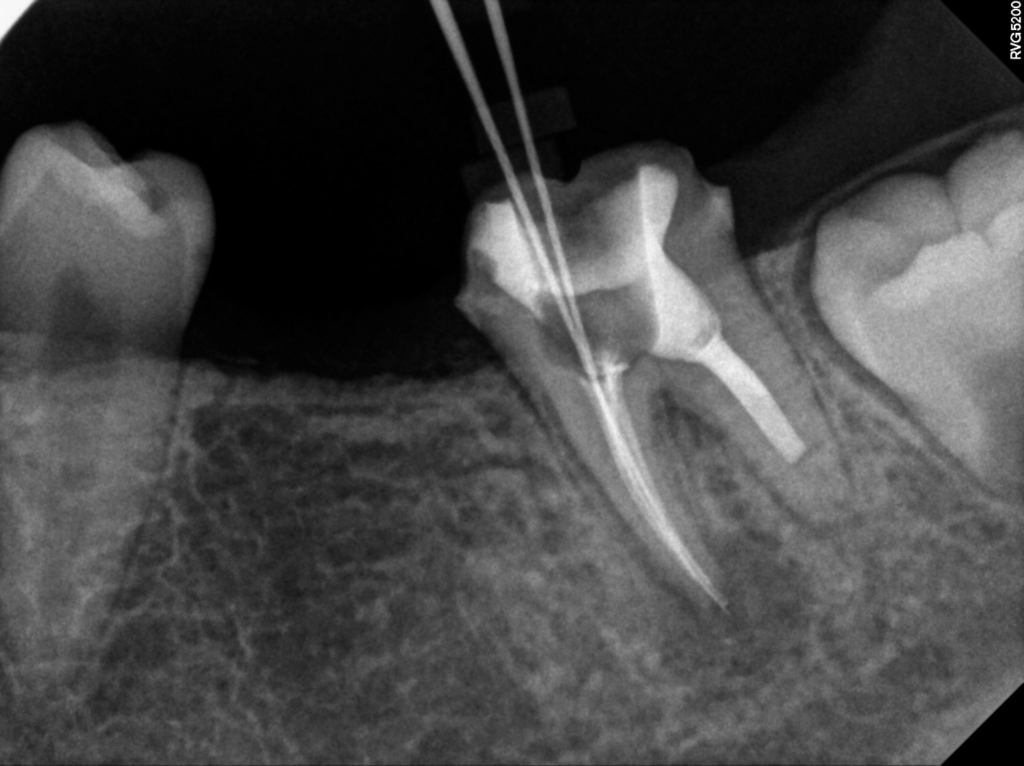

24.10.17

치료를 이어가던 중 추가로 다른 각도에서 촬영한 정밀 사진에서 문제가 되는 병변이 확인되었습니다.

해당 영상에서 근심 측 근관 부위에 이상이 있다는 점을 파악할 수 있었고, 그 부분에 대한 재치료가 필요하다는 결론에 이르게 됐습니다

치료 후 촬영한 영상에서는 근관 내부가 안정적으로 봉쇄된 모습을 확인할 수 있었습니다.

앞서 설명드린 것처럼 주변 치조골이 회복되기까지는 일정한 시간이 필요하기 때문에, 현재는 정기적으로 상태를 점검하며 불편감이 다시 생기지 않는지 등 임상적인 변화를 지속적으로 살피고 있습니다.